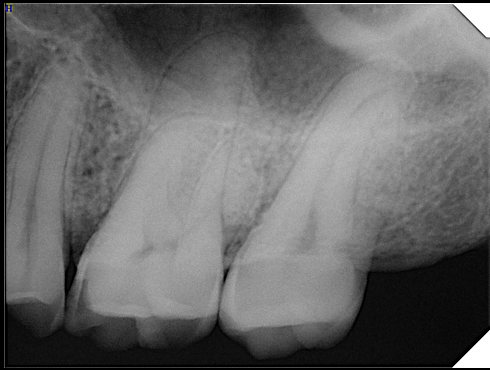

CR/DR 牙齿分割阶段记录

当前进展

- 完成了 CR/DR 牙齿相关分割训练

相关测试

遇到的问题

- 训练过程中出现过 mask 下移问题

- 部分结果会出现 box 填充异常

- mask 边缘仍然有比较明显的锯齿感

第二版算法问题测试

Updated: 2026-04-13(更新日期)

| 第一版 | 第二版 | 是否解决 | |

|---|---|---|---|

![]() | ![]() ![]() 边角识别有问题 龋齿识别不全 牙髓识别不全 | ![]() | 解决 |

![]() | ![]() 边角识别有问题 识别信息有误 自查(牙冠识别不全) | ![]() | 解决 |

![]() | ![]() ![]() 边角识别有误 大范围填充识别遗漏 | ![]() | 解决 |

![]() | ![]() 识别信息不全 | ![]() | 解决 |

![]() | ![]() ![]() 边角问题 牙胶识别不全 牙冠识别不全 | ![]() | 解决 |

![]() 换图片 | ![]() | ![]() 牙冠部分稍微白了一些就识别成小范围修补,部分判断异常 | 部分解决,修复类略敏感,牙冠部分稍微白了一些就识别成小范围修补,部分判断异常。 |

![]() | ![]() ![]() 牙冠识别不全 牙髓不全 根尖炎龋齿识别有误 | ![]() | 解决 |

![]() | ![]() | ![]() | 解决 |

![]() 换图片 | ![]() | ![]() | 解决 |

![]() | ![]() 牙冠识别有误 | ![]() | 解决 |

![]() 换图片 | ![]() ![]() 边角识别有误 | ![]() 修复类敏感 | 部分解决,图像过白,导致修复类判断异常。 |

![]() 换图片 | ![]() 牙冠识别不全 | ![]() 修复类敏感 | 部分解决,图像过白,导致修复类判断异常 |

结论:修复类出现了不鲁棒的情况,后续需要加入轮廓的扩充数据进行增强。